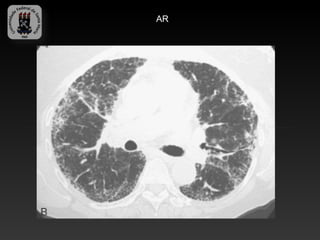

-ARTRITE REUMATOIDE

-É a mais comum doença do tecido conjuntivo

-Mulheres são afetadas 2 a 3 vezes mais do que os homens

-O envolvimento pleural é a manifestação torácica mais comum ( derrame

e espessamento)

-O grau de DPI não necessariamente correlaciona com a severidade de

acometimento articular.

- A DPI associada a AR é histologicamente indistinguível da PIU e a

fibrose pulmonar tem progressão mais lenta.

-Achados TC: nódulos reumatóides, derrame pleural e bronqueolite(áreas

de aprisionamento aéreo), padrão reticular fino.

AR